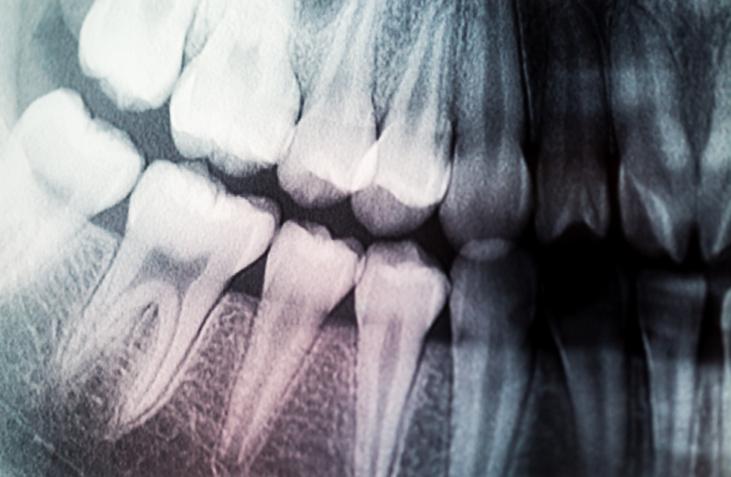

• This drug has been found to cause several dental health issues including Severe Tooth Erosion, Dry mouth, Gum Problems, etc.